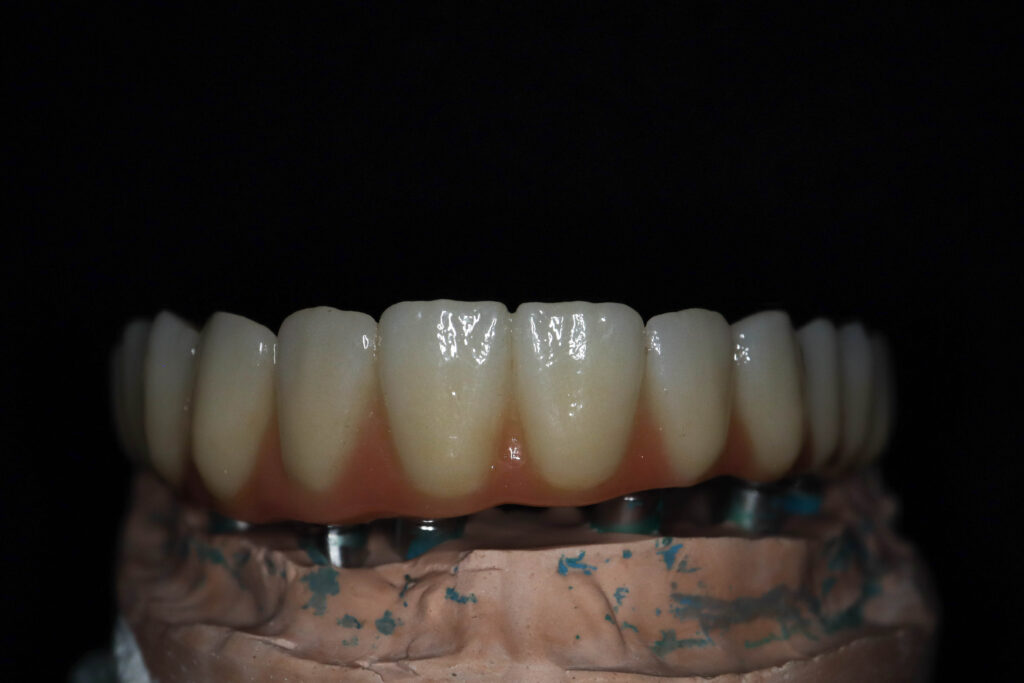

Лечение начато с выбора материала для будущей конструкции (диоксид циркония на титановой балке) и цвета.

Был установлен временный протез из PMMA, максимально воссоздающий форму и цвет (А3) будущей конструкции.

Спустя 25 дней был зафиксирован протез с опопрой на дентальные имплантаты из диоксида циркония с армированием из титана.